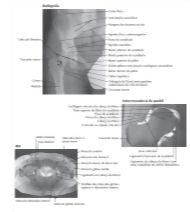

Hip Radiograph, Arthrogram, MR and PETCT Fusion